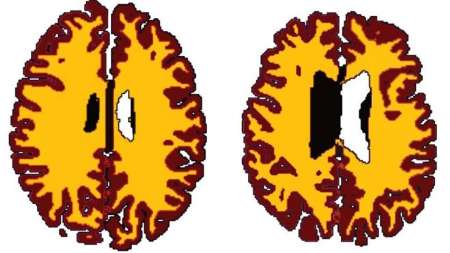

چاقی سبب پیری زودرس مغز می شود و مغز افراد چاق نسبت به هم سن و سالان لاغر 10 سال پیرتر است.

مطالعات محققان دانشگاه کمبریج نشان می دهد اضافه وزن در سرعت کاهش ماده سفید مغز موثر است و مغز یک فرد 50 ساله چاق، 60 ساله است.

چاقی سبب پیری زودرس مغز می شود و مغز افراد چاق نسبت به هم سن و سالان لاغر 10 سال پیرتر است. حجم ماده سفید مغز به طور طبیعی بر اثر افزایش سن کاهش می یابد؛ ولی چاقی این روند را تسریع می کند. ماده سفید مغز مسئول انتقال اطلاعات است.

تیم تحقیقاتی دانشگاه کمبریج برای بررسی ارتباط اضافه وزن با پیری، مغز 473 داوطلب 20 تا 87 ساله را مورد بررسی قرار دادند، داوطلبان به دو گروه لاغر و دارای اضافه وزن تقسیم بندی شدند.

نتایج نشان می دهد حجم ماده سفید مغز افراد دارای اضافه وزن نسبت به هم سن و سالان لاغرشان کمتر است و این تفاوت از دوران میانسالی به بعد مشهود تر است. محققان احتمال می دهند مغز با افزایش سن آسیب پذیرتر می شود. این مطالعه همچنین نشان می دهد تاثیر اضافه وزن بر بدن بسیار پیچیده و مضرتر از چیزی است که تا کنون تصور می شد.